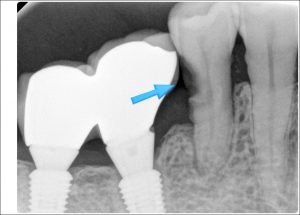

인덕원 인레이치료 잘못되었을 때 어떤 문제가 생길 수 있을까요?

인덕원 인레이치료 잘못되었을 때 어떤 문제가 생길 수 있을까요? 안녕하세요.인덕원 믿음치과 손동근 원장입니다. 치과 치료는 단순히 치료를 받는 것에서 끝나는 것이 아니라, 치료 이후 얼마나 안정적으로 유지되는지도 중요합니다. 특히 충치...